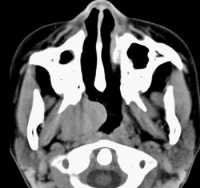

鼻咽部恶性淋巴瘤

咽淋巴环病变通常占恶性淋巴瘤的10%~15%,96%为弥漫性原淋巴细胞及组织细胞型淋巴瘤,发生部位最多在软腭、扁桃体,其次为鼻腔及鼻窦,临床有吞咽困难鼻塞鼻衄颌下淋巴结大。NHL较HD更有结外侵犯倾向,尤其是弥漫性组织细胞性淋巴瘤。结外累及以胃肠道、骨髓及中枢神经系统为多。NHL累及肠胃道部位以小肠为多,其中半数以上为回肠,其次为胃,结肠很少受累。临床表现有腹痛腹泻和腹块,症状可类似消化性溃疡肠结核脂肪泻等。个别因肠梗阻或大量出血经施行手术而确诊。肝经活组织证实约1/4~1/ 2受累,脾肿大仅见于较后期病例。胸部肺门及纵隔受累最多,半数有肺部浸润或(和)胸腔积液。尸解中近1/3可有心包心脏受侵。中枢神经系统病变多在疾病进展期,约有10%,以累及脑膜脊髓为主。骨髓累及者约1/3~2/3,与类型有关,骨骼虽还以胸椎及腰椎最常见,股骨肋骨骨盆头颅骨次之。弥漫性大细胞或组织细胞型可原发于骨骼,患者年龄较轻,多在长骨,主要是溶骨性。皮肤表现较HD为常见,多为特异性损害,如肿块、皮下结节、浸润性斑块、溃疡等。肾脏损害尸解有33.5%,但临床表现仅23%,主要为肾肿大、高血压尿素氮贮留。近年来淋巴瘤合并肾病综合征已屡有报道,随淋巴瘤缓解而好转。